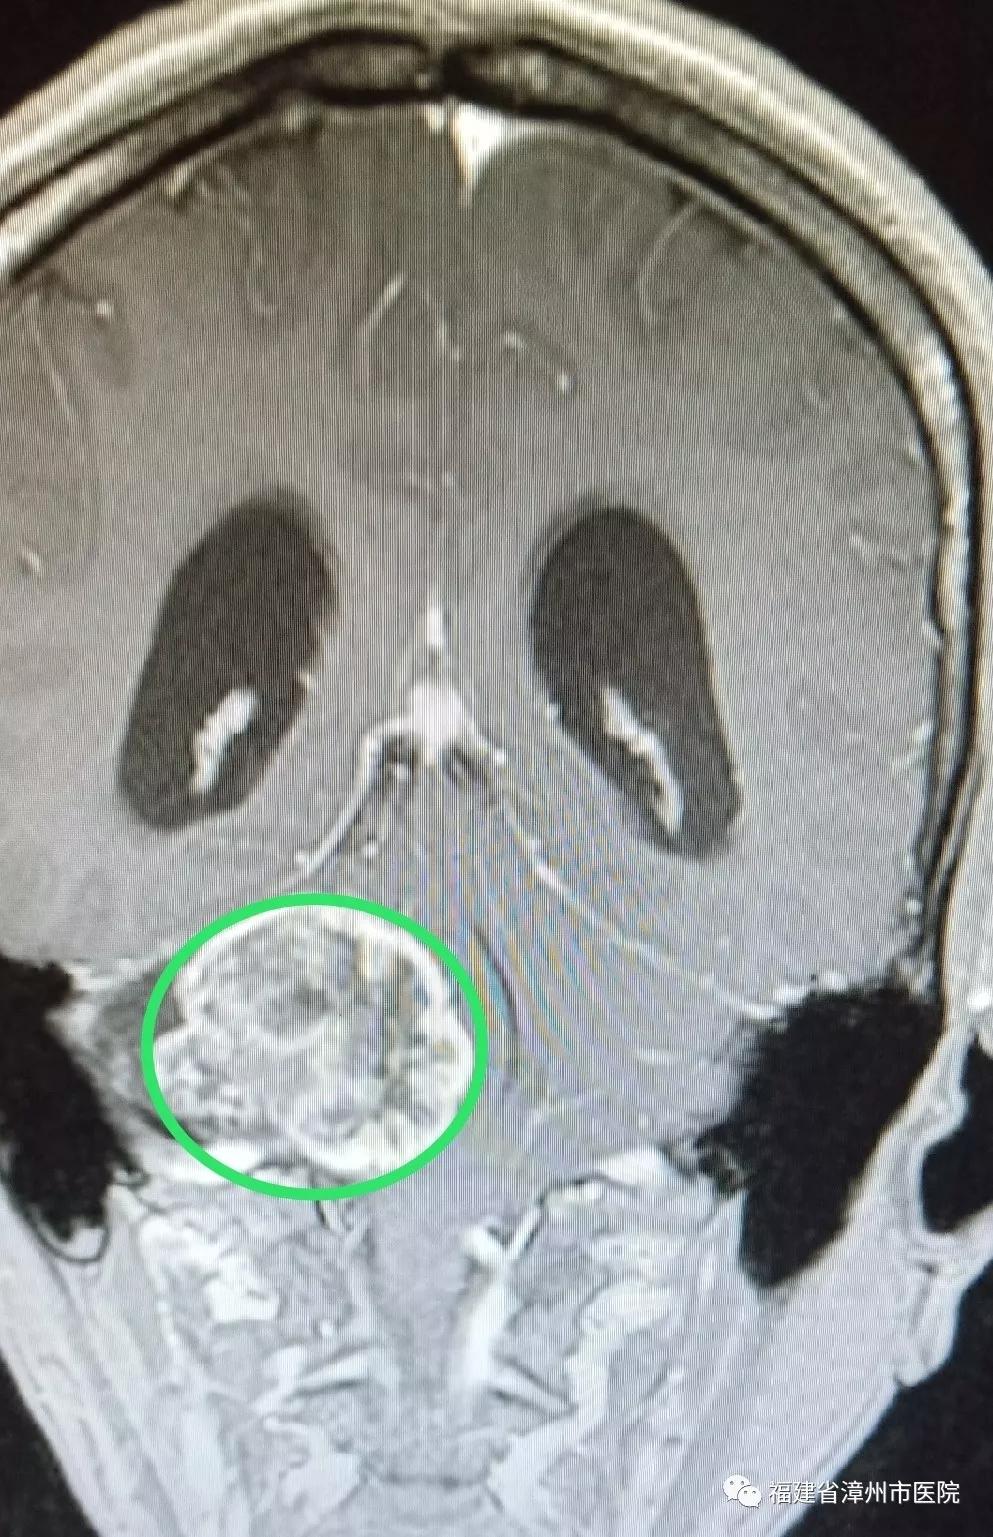

术前(肿瘤)

不久前到漳州市医院神经外科接受了颅内肿瘤切除手术的陈先生就是这种情况。陈先生今年52岁,由于做秘书工作,每天要接听数十个电话,工作压力大,情绪高度紧张。最近,打电话时他总听不清对方讲话,右边耳朵像有蜜蜂在飞,发出嗡嗡的声音。陈先生以为是手机信号不好,更换了手机,依然不奏效。有一次,他无意改用左耳听电话,感觉音质清楚了很多,这才意识到可能是自己耳朵出了问题。陈先生来到漳州市医院检查听力,我告诉他右侧听力明显下降,做磁共振检查后发现颅内有一个直径约5厘米的肿瘤,并且已经严重压迫脑干,并引起脑积水。我询问病史得知,原来4年前陈先生就感觉右耳听力下降,感觉有些耳背,他以为是工作压力大所致,一直没在意。

陈先生因为忽视,延误了最佳治疗时机。当检查发现时,肿瘤已经有5厘米大小,伴有多颅神经损害如轻微面瘫、面部麻木等症状及脑积水存在,脑干重度压迫移位。经过显微神经外科手术,目前已切除肿瘤,顺利出院。